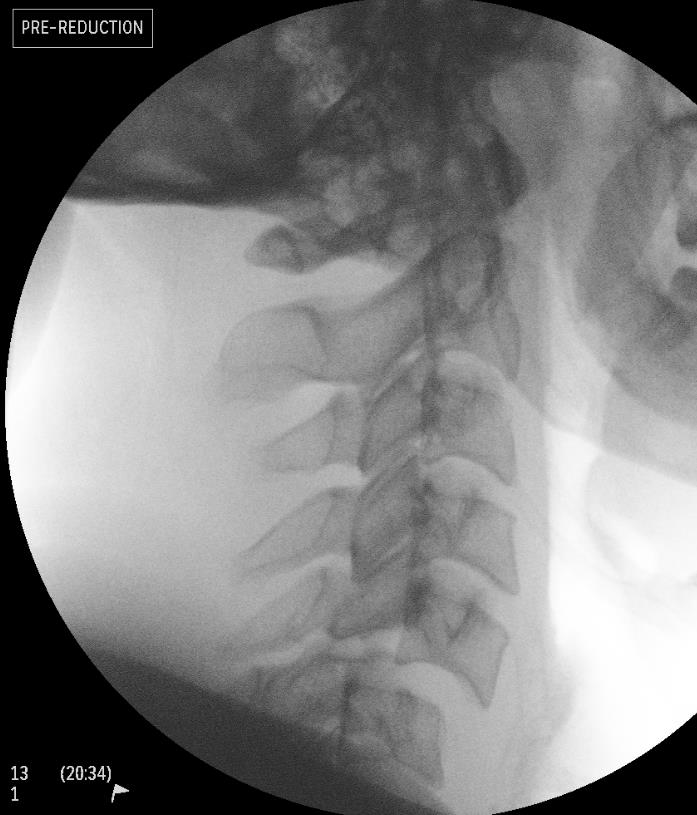

Cranio-cervical skull tong traction

Technique

Patient awake and able to communicate if neurology worsening

- best performed in operating room as can use cross table image intensifer

- Gardener Wells tongs 1" above and behind pinna

- below equator / maximum diameter of skull to prevent slippage

- place towels under head to recreate flexion deformity

- start 10 lb for head, then 5 lb for each cervical level every 10 min

- repeat X-ray after each weight increase

- monitor neurological status- if neurology worsens, release all traction

- maximum 40% body weight

- once facet unlocked, removed towels to extend head